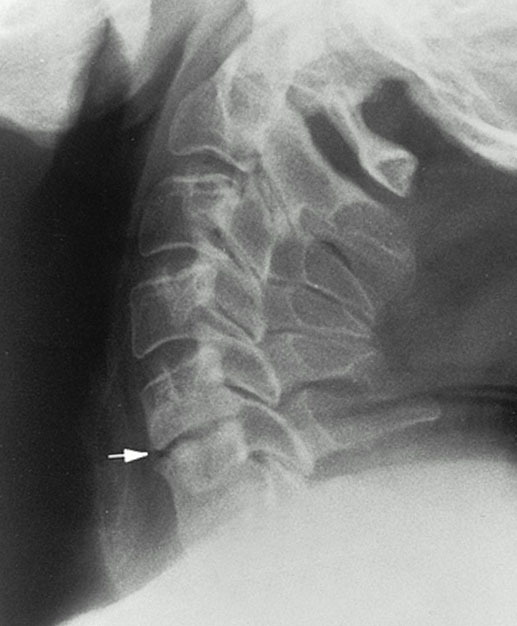

снижение высоты межпозвонкового диска (указано стрелкой). один из признаков остеохондроза.

2. Снижение высоты диска — расстояние между позвонками уменьшается

остеофиты (спондилез)